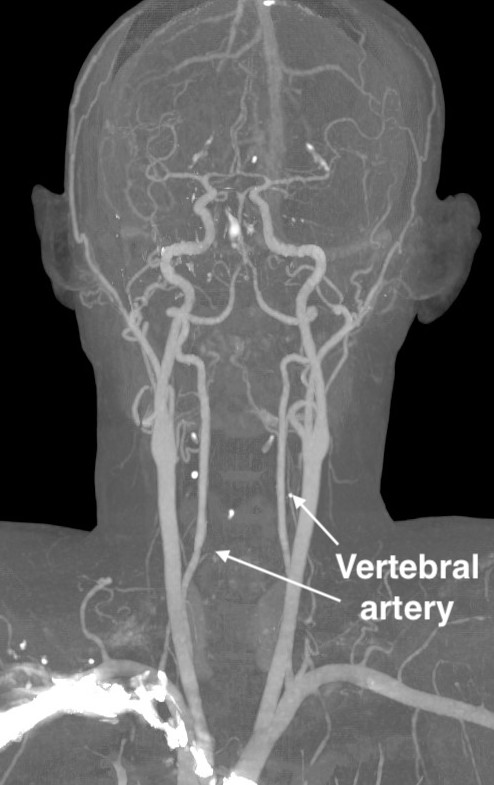

Vertebral artery

Anatomy

Origin from subclavian arteries

- anterior to C7 transverse process

- enter at C6 and travel in transverse foramina

Consequence of injury

Stroke / neurological deficit

Hemorrhage

Pseudoaneurysm and late hemorrhage

Incidence

Obermuller et al Acta Neruochirurgica 2015

- 992 cases

- 0.3% incidence vertebral artery injury

- all three cases stented and repaired

- no neurological deficit

Protection

Stay medial to uncovertebral joints

Management

Control hemorrhage

Vascular surgery

Repair +/- stent